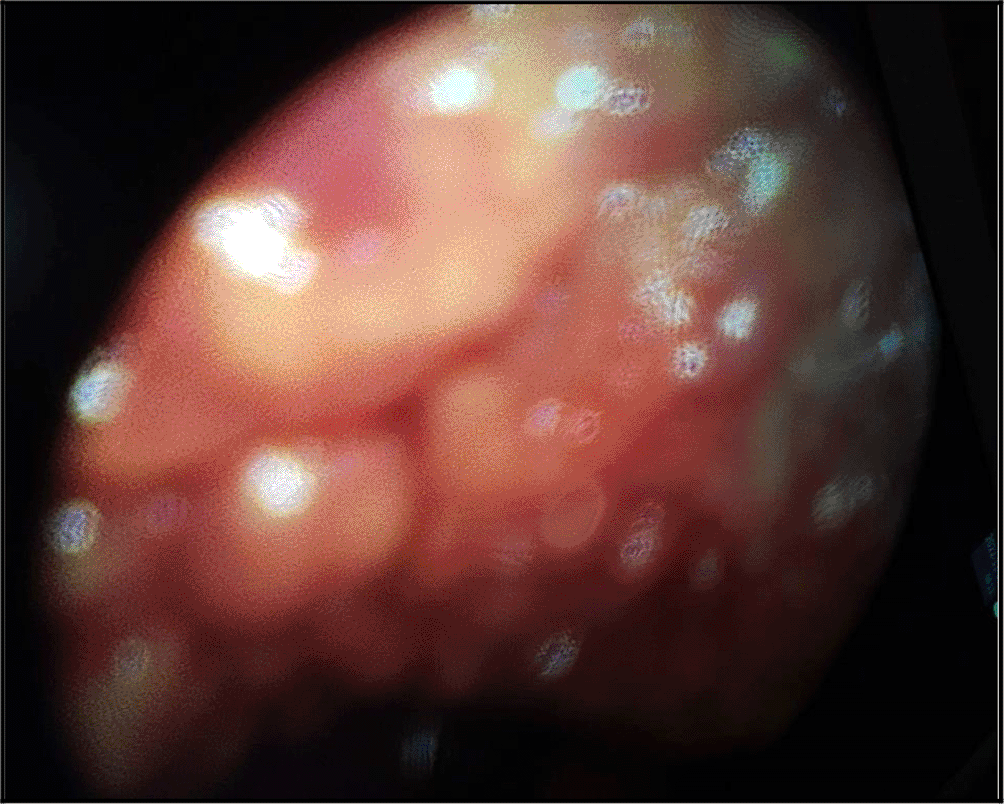

Thus, a medical thoracoscopy was performed 9 days after her admission in our department. It showed a multinodular pleura with a “bunch of grapes” aspect (Figure 4). It allowed guided pleural biopsies as well as a chemical pleurodesis in order to prevent the pleural effusion recurrence.

The diagnosis was very challenging in our patient. In fact, we initially suspected an advanced stage lung carcinoma giving the chest CT scan’s findings, or a mesothelioma because of the multinodular aspect of the pleura in the chest ultrasound and “the grape-cluster” appearance as seen in thoracoscopy. The histological exam of the pleural guided biopsy helped us to assess the right diagnosis.

The diagnosis requires the presence of a monoclonal protein or a light chain in the pleural fluid, abnormal plasma cells with an intense staining CD138.13–16 Medical thoracoscopy is actually recommended in case of a such malignant pleural effusion. In fact, it allows pleural guided-biopsy with a good-quality of sampling, pleural fluid drainage as well as pleurodesis.8,17,18 In our case, medical thoracoscopy showed a multinodular pleura with “a bunch of grapes” aspect. We decided to perform chemical pleurodesis given that most of the reported cases had a high rate of recurrence of the pleural effusion. Flow cytometry may be a useful tool in the diagnosis assessement especially in these challenging cases.19